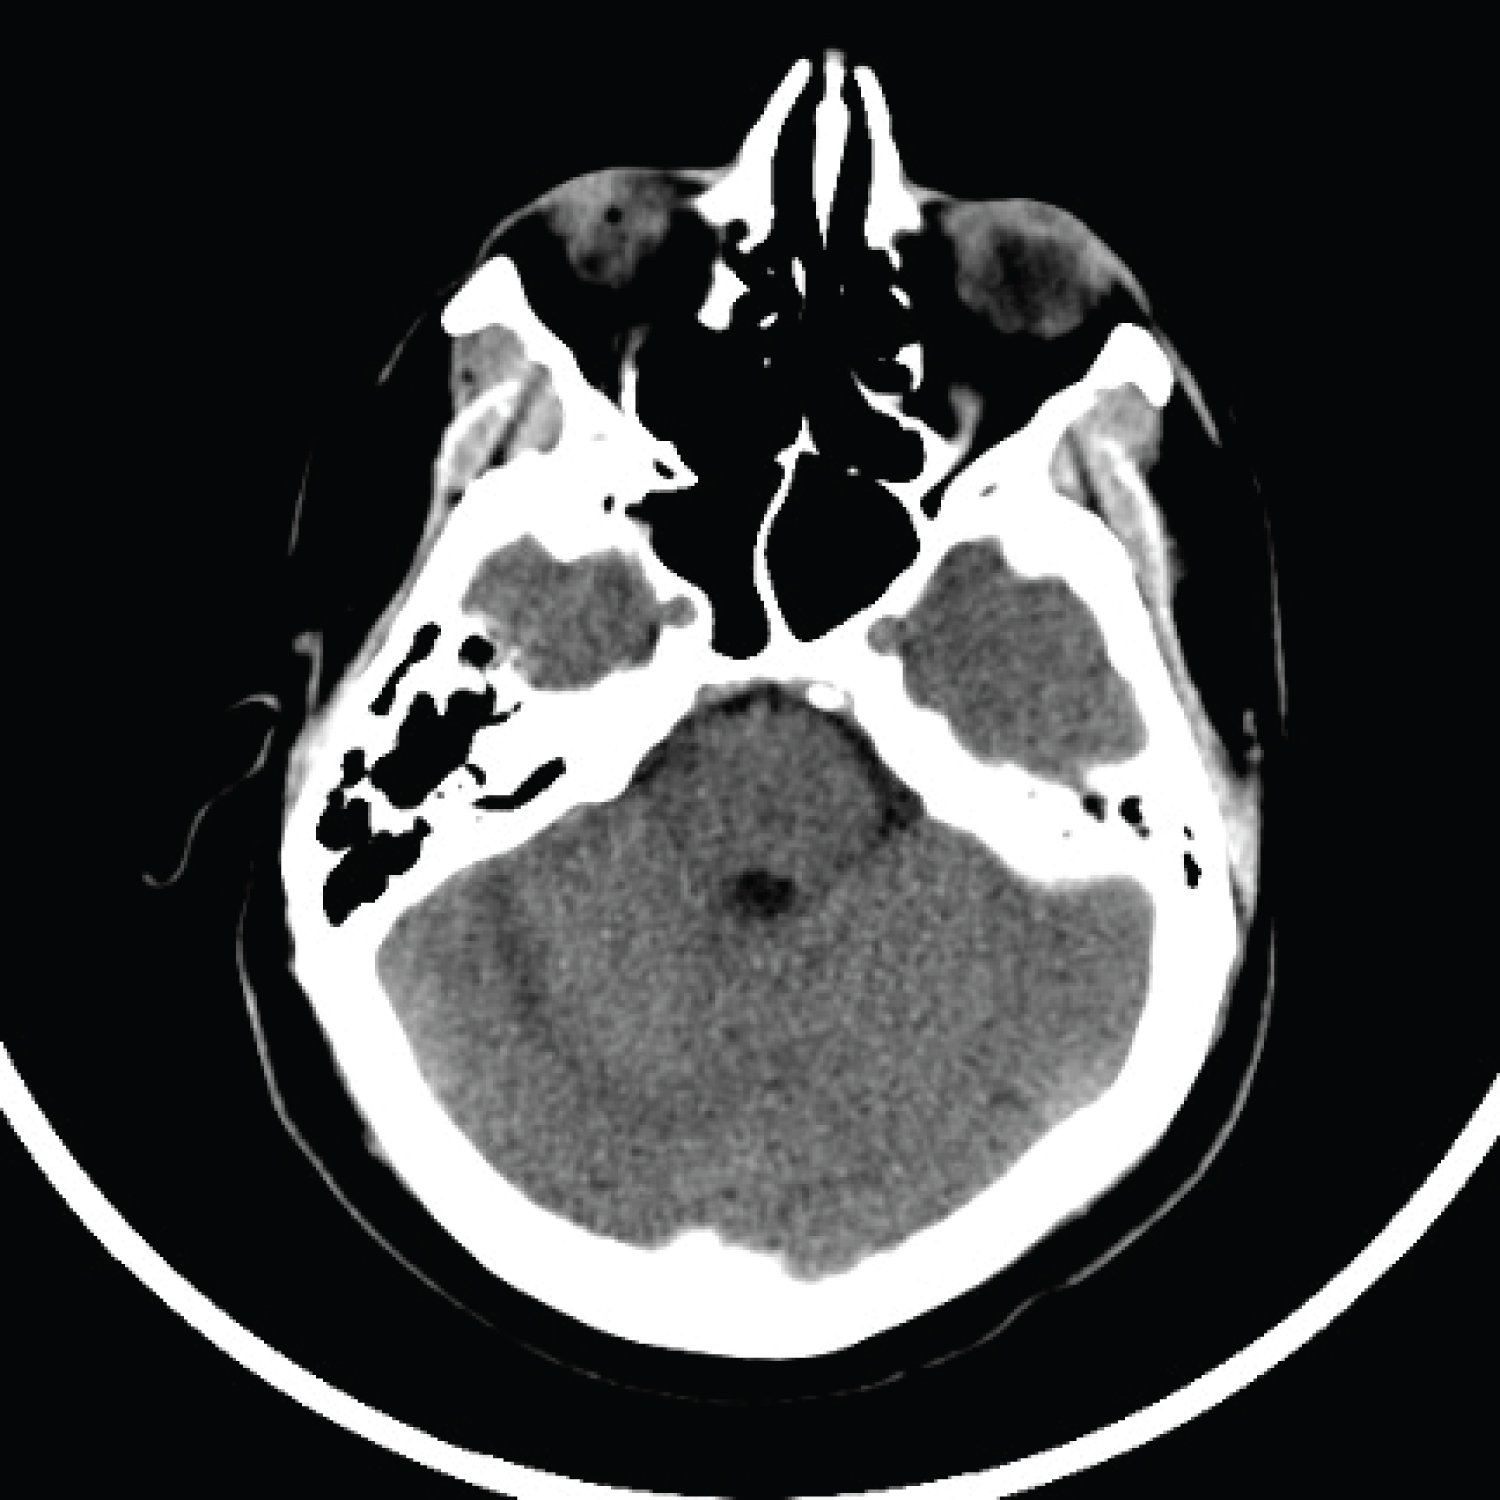

Given the patient’s obstructive hydrocephalus and 4.9 cm hemorrhage, he was transferred to the intensive care unit (ICU) for close monitoring for possible ventriculostomy and suboccipital craniotomy. The Hemovac drain was removed to decrease the possibility of CSF egress worsening his cerebellar hemorrhage. His systolic blood pressure was kept strictly below 140 mmHg and hypertonic saline was administered as needed to reduce cerebral edema. He remained in the ICU for 11 days with serial head CT imaging showing improvement of his cerebellar hemorrhage and hydrocephalus (Figure 2). Midway through the clinical course, a 6-vessel digital subtraction angiography was performed and ruled out the presence of an aneurysm, dural venous sinus thrombosis, or arteriovenous malformation (AVM), which could have significantly altered the management approach (Figure 3). The patient’s mental status rapidly improved during his ICU course and remained stable. Throughout his hospitalization, extensive discussions were held on whether the patient was a suitable candidate for surgery or ventriculostomy given his neurological exam. Ultimately, the decision was made against surgery given his rapid improvement and ongoing stability.

Figure 2: Head CT without IV contrast POD15 demonstrating improvement of right cerebellar hemorrhage during inpatient course. View Figure 2